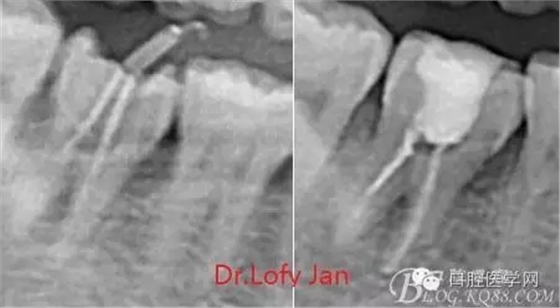

《數(shù)字化根尖片、曲面斷層片、CBCT測量牙齒長度準確性的比較研究》文中顯示:平行投照數(shù)字化根尖片影像長度和牙齒實際長度之間無顯著性差異(P0.05);數(shù)字化曲面斷層片影像長度和牙齒實際長度之間有顯著性差異(P0.05),平均失真率為17.05%。CBCT冠狀面測量結(jié)果中除上頜前磨牙區(qū)、下頜前磨牙區(qū)與真實長度差異無統(tǒng)計學意義(P0.05)外,其余6個分區(qū)差異均有統(tǒng)計學意義(P0.05);矢狀面測量結(jié)果中上頜磨牙區(qū)、下頜磨牙區(qū)、下頜前磨牙區(qū)、下頜尖牙區(qū)、下頜前牙區(qū)與真實長度比較差異均有統(tǒng)計學意義(P0.05)。結(jié)論平行投照數(shù)字化根尖片較曲面斷層片和CBCT能更加精確地反映牙齒的真實長度。

病例分析:曲面斷層片在x線輔助診斷與檢查中目前大多數(shù)文獻和著作都建議只能作為初診拍片檢查手段,不能作為終末疾病的確診與手術(shù)療效的評價指標,臨床大部分中小型門診都因為設備不齊全導致信息偏差很大。